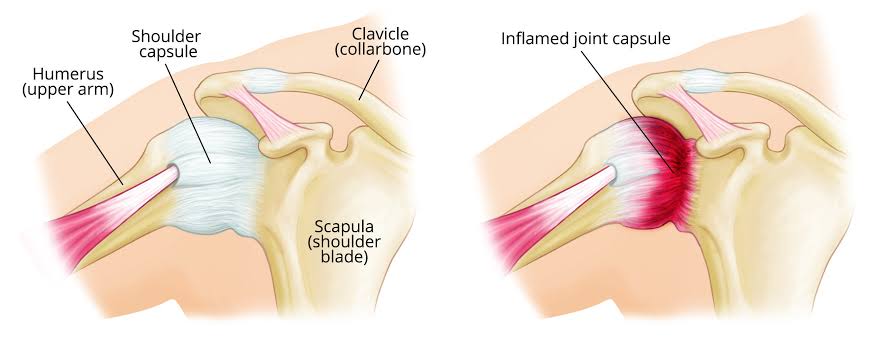

事实上真正的肩周炎是原因不明的,主要的病理表现是整个肩关节囊的明显的炎症反应,并且出现粘连,而且这个疾病是自限性的疾病,虽然早期患者会出现明显的疼痛,在中期会出现肩关节明显的范围活动受限,但是在晚期的时候患者的肩关节功能慢慢会自动恢复。正是因为这个疾病有这样的特殊表现,类似于肩关节被冻住了之后又慢慢的解冻,所以也被称之为冻结肩。

我们只知道如果患者患有高血压、糖尿病、冠心病或者是甲状腺疾病,非常容易出现肩关节的周围囊炎,尤其是糖尿病患者,有35%的糖尿病患者会出现肩关节的周围囊炎,而且糖尿病的时间越长,恢复的效果越差。另外肩关节的周围囊炎非常容易在人们的50岁左右这个年纪开始出现显现,所以也被称为50肩。

出现肩关节周围囊炎的患者首先表现的是肩关节的疼痛,最开始往往不是特别的严重,但是症状会越来越明显,一般会在2~3周之后疼痛明显的加重,患者做任何活动都会出现明显的肩痛,尤其是在夜间的时候会疼痛的特别明显。之后疼痛有可能会减轻,但慢慢的这个疾病会进展到粘连的这个阶段,整个肩关节的活动都会受到明显的限制,患者梳头都非常的困难。

对于肩关节周围囊炎的诊断:可以通过肩关节的肌骨超声或者是核磁来判断,肌骨超声价格便宜,检查迅速,适合于复诊。核磁可以适合于明确诊断,而且可以判断是否存在肩关节的撞击以及肩袖损伤,适合于第一次确诊时来检查。

治疗:在疼痛比较明显的时候,可以通过口服、外用非甾体镇痛药帮助患者减轻疼痛,针灸、手法治疗、物理治疗都可以起到很好的作用,如果患者疼痛难以控制,可以考虑进行肩关节封闭注射治疗。关节粘连比较严重的时候,可以寻求专业的康复师或者是康复治疗师的帮助,通过肩关节松动术来慢慢的帮助患者松解粘连的肩关节,逐渐恢复肩关节的功能。